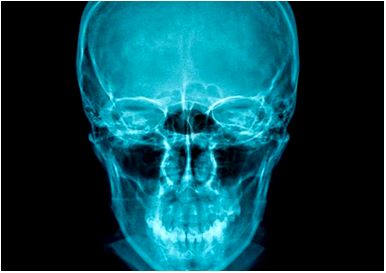

Background and aims: When a bone fracture occurs, the bone matrix is damaged and destroyed, cells die, the periosteum and endosteum rip, and the ends of the broken bone may move. Cascades of biological processes are necessary for bone development and healing. Numerous biological indicators found in blood and tissue fluids may be helpful in assessing how well bone mending is going. By analysing bone biochemical indicators in connection to radiographic results, this study aims to assess bone healing in patients with various forms of facial bone fractures.

Patients and methods: A clinical laboratory study conducted in 2025 at Military Hospital in Sana'a, Yemen, included twenty patients with surgically treated facial bone fractures. The study documented injury types, fracture sites, and treatment methods. Radiographic assessments were performed upon admission and during postoperative follow-ups. Blood samples were collected at zero days, 14, 45, and 90 days for biochemical analysis of alkaline phosphate (ALP) activity, calcium, phosphorus, and c-reactive protein (CRP) levels in serum.

Results: The study comprised 20 patients, predominantly male (80%) with an average age of 37.6 years, mainly suffering fractures from road traffic accidents (85%). The zygomatic bone was most frequently affected (55%). Fracture types included compound (40%), comminuted (35%), and simple (25%). Postoperatively, 80% had open reduction, with nerve injury as the sole complication (10%).

Conclusions: Fracture causes mainly stemmed from road traffic accidents; the zygomatic bone was the most frequently fractured site. Fracture types included compound was the most common, most patients underwent open reduction, and the only complication noted was nerve injury. Serum and biochemical markers can be used for evaluation of progress of bone formation and help clinician to assess the type of treatment.